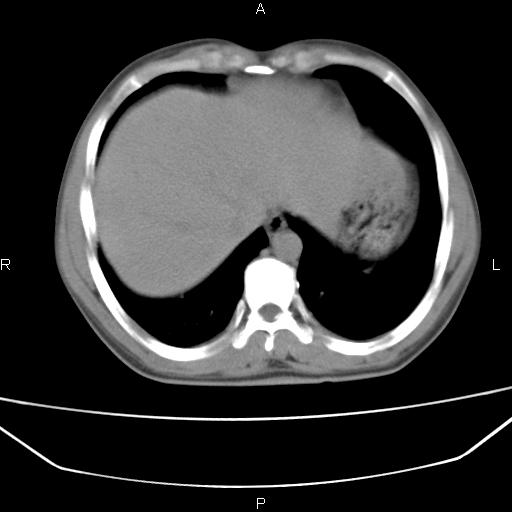

患者,男,40岁。间断发热,咳嗽二十余日。体温最高达38.9° 在当地诊所抗炎治疗三天后体温降至正常,患者自行停药。今又发热。胸片示,左下肺阴影。

左下肺片状高密度影,境界模糊,密度不均,考虑感染性病变可能性大,建议抗炎治疗后复查。左肺门增大,不除外占位性病变,必要时支气管镜检。

建议强化或纤支镜观察,考虑肿瘤性病变可能性大